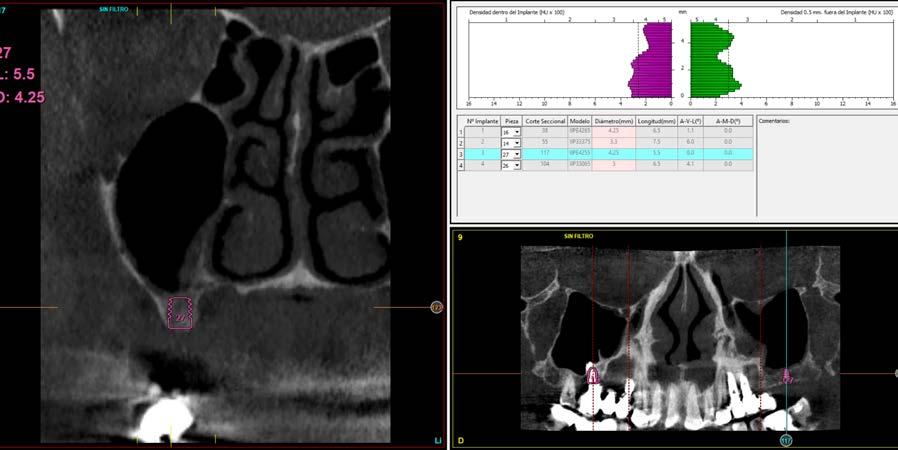

Explantación atraumática y recambio de implantes mal posicionados y afectados por periimplantitis sumado a la utilización de implantes estrechos y cortos. Enfoque mínimamente invasivo de un caso de atrofia ósea moderada

42 | INVESTIGACIÓN CLÍNICA